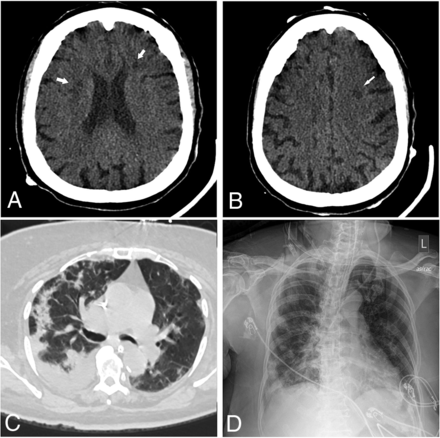

Of the 24 patients with acute neuroimaging findings, 7 patients were found to have intracranial hemorrhage (Fig 1), 7 patients were found to have acute infarction (Fig 2), 6 patients were found to have leukoencephalopathy (Fig 3), 3 patients had intracranial hemorrhage and infarction, and 1 patient had intracranial hemorrhage, infarction, and leukoencephalopathy (Table 2). Sixty-nine patients did not have acute neuroimaging findings (Fig 4). There was no significant difference (P = .225) between the distribution of Radiological Society of North America categories of chest CT findings between patients without acute neuroimaging findings (n = 66) and those with acute neuroimaging findings (n = 14), with the “typical” category being the most prevalent in both groups (Table 2).21

A 64-year-old man presented with fever and shortness of breath. Axial FLAIR (A) and diffusion-weighted (B) images demonstrate extensive symmetric confluent T2/FLAIR signal abnormality and restricted diffusion involving the corona radiata bilaterally. C, Chest CT shows bilateral peripheral ground-glass opacities and a small amount of consolidation involving all lobes, with a CCS score of 15. D, Portable chest radiograph demonstrates bilateral lower-zone-predominant peripheral opacities with a PXS score of 8.8.